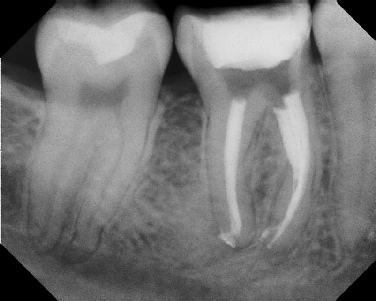

COMPLICATED ANATOMY LARGE LESIONS CALCIFIED CANALS PERFORATION / RESORPTION SEPARATED INSTRUMENTS SURGICAL CASES RETREATMENT / pOST REMOVAL OPEN APICES ACCESS THRU CROWNS Root Canal Case Portfolio

Pre-op Post-op 1 Post-op 2